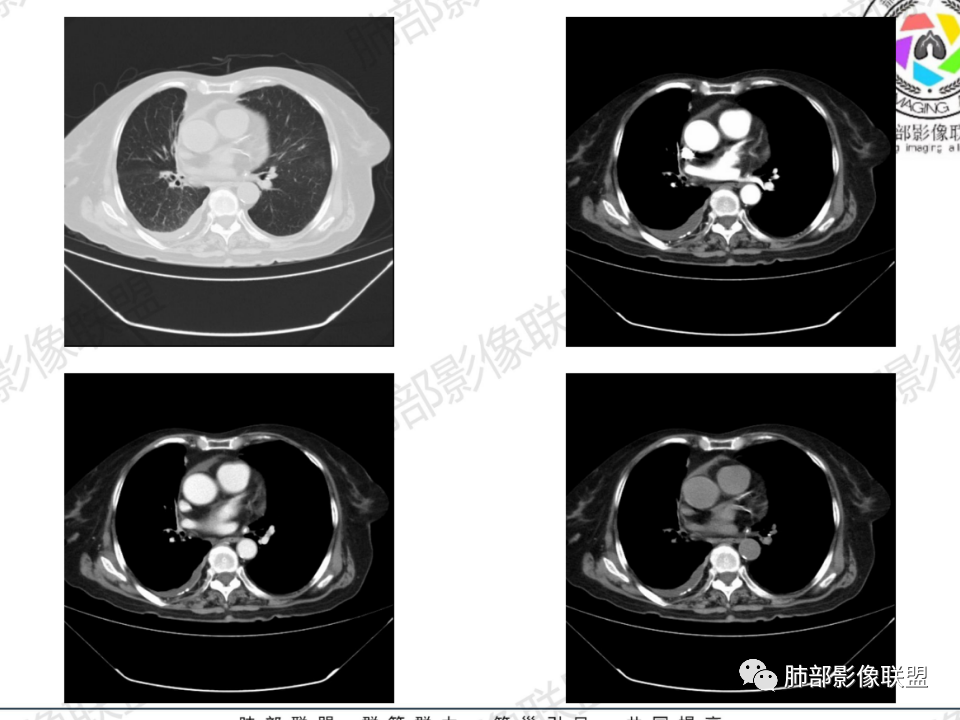

老年患者,病程中等,有咳嗽/喘息/低热症状,肿瘤标志物升高,感染标志物不高,右上肺新生物,中央型,边界清楚,有分叶,支气管截断,内有坏死,不均匀强化,考虑肺癌,鳞癌?

那个人:老年女性,亚急性病程,咳嗽发热。有垂体前叶功能减退,目前激素替代治疗,长期激素,量小,不知道累积量,没有目前激素水平指标。既往有淋巴结结核病史。肿瘤标记物Ca125升高。血沉升高,C反应蛋白轻度异常。影像,右肺上叶靠近肺门团块影,右肺门淋巴结钙化肿大,支气管狭窄,局部增厚,团块影外朝内改变,强化明显,血管破坏不明显,有粘液。和纵隔胸膜分界清楚,周围肺组织有斑片渗出影,右侧胸腔积液,考虑炎性?结核?支气管镜检查除外恶性飞鹰行动:老年患者,影像表现 右肺上叶占位性病变,边界清楚,有分叶征,内见细小钙化,右肺上叶支气管截断,增强病灶不均匀强化,病灶内有条状坏死区(扩张的支气管?),纵膈内未见增大淋巴结,考虑炎性病变,结核可能。一切∮随缘:右肺上叶实性肿块形态不规则,呈三角形,边缘分叶,边界伴有磨玻璃影,近段支气管未见明显显示,可能堵塞,病变平扫密度均匀,增强后可见低密度坏死无强化,周围略强化,右肺下叶散在结节。心包积液,及右侧胸腔积液,临床:有低热,低蛋白血症,肿瘤标记物高,考虑恶性:腺癌,神经内分泌癌(强化偏弱了),淋巴瘤,鉴别:结核红星:老年女性患者右肺上叶,肺门上区 分叶状肿块 ,右肺上叶支气管显示不清,增强扫描肿块,中等程度强化可见小斑片状坏死区,病灶内部可见斑点状钙化灶,病灶周围可见斑片状及小斑点状影,纵膈淋巴结增大,其他区域,胸膜下可见斑点状钙化。考虑肉芽肿性病变,结核的可能性大。老年患者最排除肿瘤性病变腺癌。土娃:右上肺不规则肿块影,边缘分叶,边界磨玻璃影欠清,病灶分叉状,内见点状钙化影及坏死灶,支气管堵塞,病灶增强强化不明显。考虑瘤样结核,鉴别淋巴瘤。张小兵:老年女性,亚急性病程,右肺上叶见不规则肿块,边缘平直凹陷为主,周围GGO边界不清,内见点状钙化及坏死灶,增强持续性渐进强化,右侧少量胸腔积液,双肺门及纵隔肿大淋巴结伴钙化,综合考虑慢性炎症。saf:老年患者,影像表现 右肺上叶占位性病变,边界清楚,有分叶征,增强病灶明显不均匀强化,纵膈内未见增大淋巴结,考虑炎性病变,结核可能。小兜:老年女性,咳嗽喘息一月,发热三天,肿瘤标志物升高,长期激素替代治疗。CT示右肺上叶近肺门不规则实变影,周围伴磨玻璃影,增强持续性渐进强化,内部血管破坏不厉害,内部可见多发条形低密度灶,右侧胸腔可见少量积液,双肺门及纵隔可见钙化淋巴结,考虑为炎性病变,结核可能玫:女,79咳嗽,喘息一月,发热三天入院,右肺上叶不规则形软组织密度肿块影,边界清晰,边缘见分叶及细短毛刺,病灶内见点状钙化影及稍低密度区,病灶边缘呈磨玻璃样改变,增强扫描,病灶呈不均匀性强化,考虑炎性病变,鉴别鳞癌。大雄:老年女性,既往诊断淋巴结结核,提示已治愈,近2年服用激素,诱导结核复燃→发热;纵隔肺门淋巴结肿大钙化,压迫支气管,右肺上中下叶支气管均狭窄→喘息咳嗽;尖段支气管受累闭塞→肺不张、支气管粘液栓;累及胸膜,结核性胸膜炎并胸水→右侧胸痛;实验室,血沉快,CA125高,低蛋白,符合;下一步,支气管镜尖段支气管刷检抗酸染色周太狼:老年女性,亚急性病程,肿瘤标志物升高。CT示右肺上叶尖段不规则肿块影,有分叶、收缩,周围伴磨玻璃影,增强渐进强化,内部可见多发条形低密度灶,右侧胸腔及心包少量积液,纵隔内淋巴结稍增大。倾向于恶性病变,肺癌伴阻塞性炎变可能。丽:老年女性,右肺上叶不规则软组织肿块,边缘清晰,内密度不均,可见点状钙化及粘液栓,周围可见片状高密度影,增强后均匀强化,内多发低密度,纵膈多发钙化淋巴结,考虑结核可能大,建议结合支气管镜检查除外肿瘤宇宙:右胸廓缩小,右肺上叶团块影及不张,平直边,周围磨玻璃影,纤细胸膜牵拉,上叶尖段支气管堵塞,明显延迟强化,可见支气管粘液栓,两肺门钙化淋巴结,右侧胸水,考性炎性肉芽肿,鉴别腺癌王秀仙:右肺上叶肺门区肿块,上叶支气管开口阻塞,形态不规则,密度不均,内可见支气管粘液栓及多发小灶性坏死,周围磨玻璃影边缘模糊,渐进强化,右侧胸腔积液、胸膜钙化,考虑炎性肉芽肿性病变,慢性炎症。鉴别鳞癌,结核。刘丹:老年女性,右肺上叶肿块伴钙化,右肺上叶支气管截断,增强后均匀强化,周边可见点片状模糊影,右侧胸腔积液,右肺门淋巴结增大,考虑占位并阻塞性炎症,肿瘤?结核?建议纤支镜检查。小飞:右肺上叶纵隔旁软组织肿块,边缘深分叶、长毛刺及毛刷样短毛刺,边缘磨玻璃影,磨玻璃边界模糊,支气管截断,平扫密度不均,可见点状钙化,增强不均匀明显强化,心影增大,心包积液,右侧胸腔积液,考虑恶性肿瘤,腺癌?秦化君:右肺上叶不规则分叶软组织密度肿块,边缘清晰,胸膜牵拉,周围花花草草,上叶尖段支气管阻塞,内可见点状钙化,增强后密度不均可见支气管粘液栓及坏死区,内见血管分枝。中间段及中叶,下叶支气管狭窄,壁见钙化。右肺门淋巴结肿大,右侧胸腔积液,心包粘连肥厚。考虑1右上肺恶性病变,鳞癌?2右肺多叶段支气管狭窄,考虑支气管内膜结核?3胸腔积液及肺门淋巴结肿大,转移?风儿:老年女性,右肺上叶肿块,形态不规则,外围大内带小,边缘分叶膨隆平直及毛糙,密度不均,内见支气管粘液栓及多发小灶性坏死,坏死边缘清晰 ,渐进强化,上叶尖段支气管阻塞,叶支气管壁有局限性增厚,邻近胸膜腔微积液;纵隔及双肺门淋巴结肿大,部分钙化,右侧胸腔积液、心包积液、胸膜钙化,考虑炎性,肉芽肿性结核可能性大。鉴别鳞癌,女性及血供均不支持;腺癌,坏死边界太清晰。流心明智:老年女性,79岁,咳嗽、气短1月,发热3天。胸CT:右肺上叶见不规则肿块,边缘有膨隆、有平直凹陷,周围GGO边界不清,病灶内见点状钙化、粘液栓,尖段支气管未见,增强持续性渐进强化,右侧少量胸腔积液,双肺门及纵隔肿大淋巴结伴钙化,肺动脉增粗。考虑:右上叶尖段堵塞并慢性炎症,支气管TB并结石?鉴别Ca

右肺体积小,提示既往结核

支气管影

前,后段都在,没有堵塞

支气管壁增厚,周围磨玻璃边界不清,提示炎症。胸膜下钙化符合结核

近期发热符合感染

这个层面往上应该是尖段,显示不清

背段支气管周围增厚伴钙化,符合结核改变

胸腔积液并胸膜钙化,符合结核;

结核是肯定有。现在最大问题是尖段

近端显示不清,但是远端是粘液栓,可以认为是还行的

如果是近端鳞癌,远端应该会堵塞,不会整个肿块里面还有较为通畅的支气管

这个区域我们看到密度与周围一致,并不是肺癌伴周围不张的感觉,所以鳞癌暂时是不支持的

临床信息:老年女性,亚急性病程,咳嗽发热。有激素使用史。既往有淋巴结结核病史。肿瘤标记物Ca125升高。血沉升高,C反应蛋白轻度异常。 影像所见:右侧胸廓相对狭小,右肺上叶不规则团块影贴附纵隔旁,轻度分叶,整体密度较均匀,偶见钙点。

相应上叶尖端及前段支气管开口未能追踪(阻塞),开口处见钙化。病灶渐进性强化,并衬托出较完整尖段及前段含液支气管影。支气管开口区域未见异常高密度强化(如类癌等)及相对乏血供区(如鳞癌)。病灶区未见液化坏死。右上纵隔及胸廓入口区未见病灶胸膜外突破(栽赃)。

右肺上叶后段等区域散在片状影,边界不清(提示渗出性病灶)。

纵隔及双肺门见钙化淋巴结。心包积液,右侧胸腔积液(提示存在活动新病灶)。双侧胸膜下见多发斑点状钙化,胸廓变形(提示存在结核基础病变可能)。 诊断意见:综上,右肺上叶块状影更符合继发性肺结核。 最后小结:既往诊断淋巴结结核,提示已治愈。近2年服用激素,可疑诱导结核复燃,也可引起发热。纵隔肺门淋巴结肿大钙化,压迫支气管,右肺上中下叶支气管均狭窄,所以引起喘息咳嗽。尖段支气管受累闭塞,导致肺不张、支气管粘液栓,出现条状无强化区。病变累及胸膜,导致结核性胸膜炎并胸水,引起右侧胸痛。实验室检查血沉快,CA125高,低蛋白,均符合结核。下一步,建议支气管镜尖段支气管刷检并抗酸染色。(本段摘自於雄老师精彩发言)